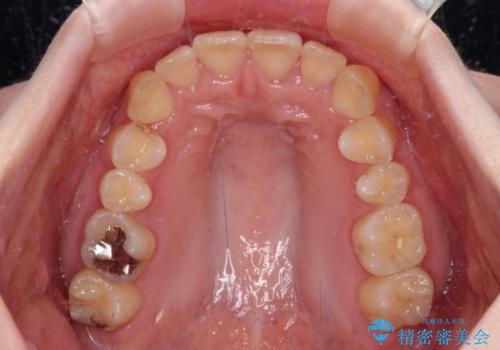

カリエールディスタライザーやワイヤー矯正を併用したことで、確実かつ短期間で治療を終えることができました。